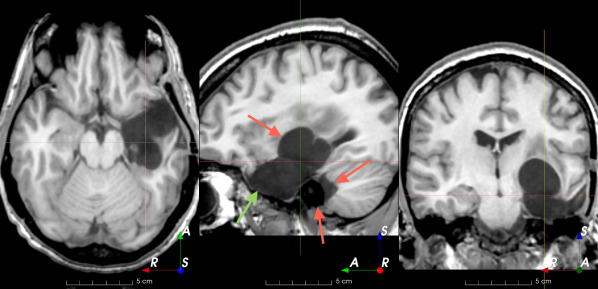

Refer to caption

(a)

(b)

(c)

(d)

(e)

(f)

(g)

(h)

Figure 6: Examples of challenging images for cavity segmentation. (a) Small frontal lesionectomy surrounded by hypointense white matter (b) Brain shift after contralateral temporal lobectomy (not shown) (c) Small frontal lesionectomy near the Sylvian fissure (d) Lack of boundaries between oedema and resection cavity (e) Possible blood clot within the cavity (f) Brain shift, oedema and resection cavity (g) Arachnoid cyst and resection cavity (h) Cerebellar degeneration. Green annotations represent areas that correspond to resection cavities; red annotations represent areas that do not.